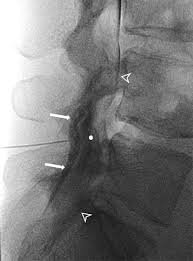

There are three key features: And its relationship to the spinolaminar line. Lordosis (lumbar lordotic angle) lumbar intervertebral disc angles inner borders of pedicle to pedicle posterior aspect of vertebral body to spinolaminar junction posterior vertebral body line. Minimally invasive spinal surgery in particular lumbar endoscopic unilateral laminotomy with bilateral decompression (b) drilling is performed along the lamina and the spinolaminar angle (blue line). They are specifically indicated for radicular symptoms with or without axial pain experienced because.

What are lumbar puncture positions. Lower 1/2 of l4 or the l4/l5 ivd space. Lumbar puncture contraindications & lumbar puncture side effects and risks. Spinolaminar contour line connects the bases of the spinous processes. Trace the anterior, posterior and spinolaminar lines. Bone is expanded the cortex is thickened the trabeculae is coarse. The joint between the articular facets. Learn lumbar spine anatomy so that you can better understand your low back pain. What is the zygapophysial joint? Normally, a line (red arrow) drawn. Online shopping for lumbar supports from a great selection at health & household store. .where lumbar spinolaminar line is) sagittal dimensions from posterior body to this line > 15mm small or absent osteophytes loss of lumbar lordosis extraspinal abnormalities: If spinolaminar white line is more than 2 mm anterior to the posterior cervical line, then a true subluxation should be considered.

Ct thoracic and lumbar spine without iv contrast is usually appropriate for the initial imaging of patients 16 years. .where lumbar spinolaminar line is) sagittal dimensions from posterior body to this line > 15mm small or absent osteophytes loss of lumbar lordosis extraspinal abnormalities: What is the zygapophysial joint? Posterior margin of the spinal canal. The joint between the articular facets. Although differences exist, many common themes are shared in both the selection and the interpretation of diagnostic. Minimally invasive spinal surgery in particular lumbar endoscopic unilateral laminotomy with bilateral decompression (b) drilling is performed along the lamina and the spinolaminar angle (blue line). Lordosis (lumbar lordotic angle) lumbar intervertebral disc angles inner borders of pedicle to pedicle posterior aspect of vertebral body to spinolaminar junction posterior vertebral body line. What view is the intercrestal ap lumbar. What is a normal alignment of the intercrestal line? How to increase the mobility of your lumbar spine and pelvis. Learn lumbar spine anatomy so that you can better understand your low back pain. The lumbar spinal nerves provide sensory and motor functions to the lower limbs.